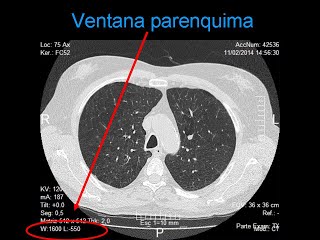

- VENTANA DE VISUALIZACION: Ventana mediastinica W:400 L: 40

Ventana parenquima: W: 1.600 L: 550

EVIDENCIAS DE IMAGENES DIAGNOSTICAS DE UNA TOMOGRAFIA DE UN TORAX SIMPLE

VENTANA PULMONAR